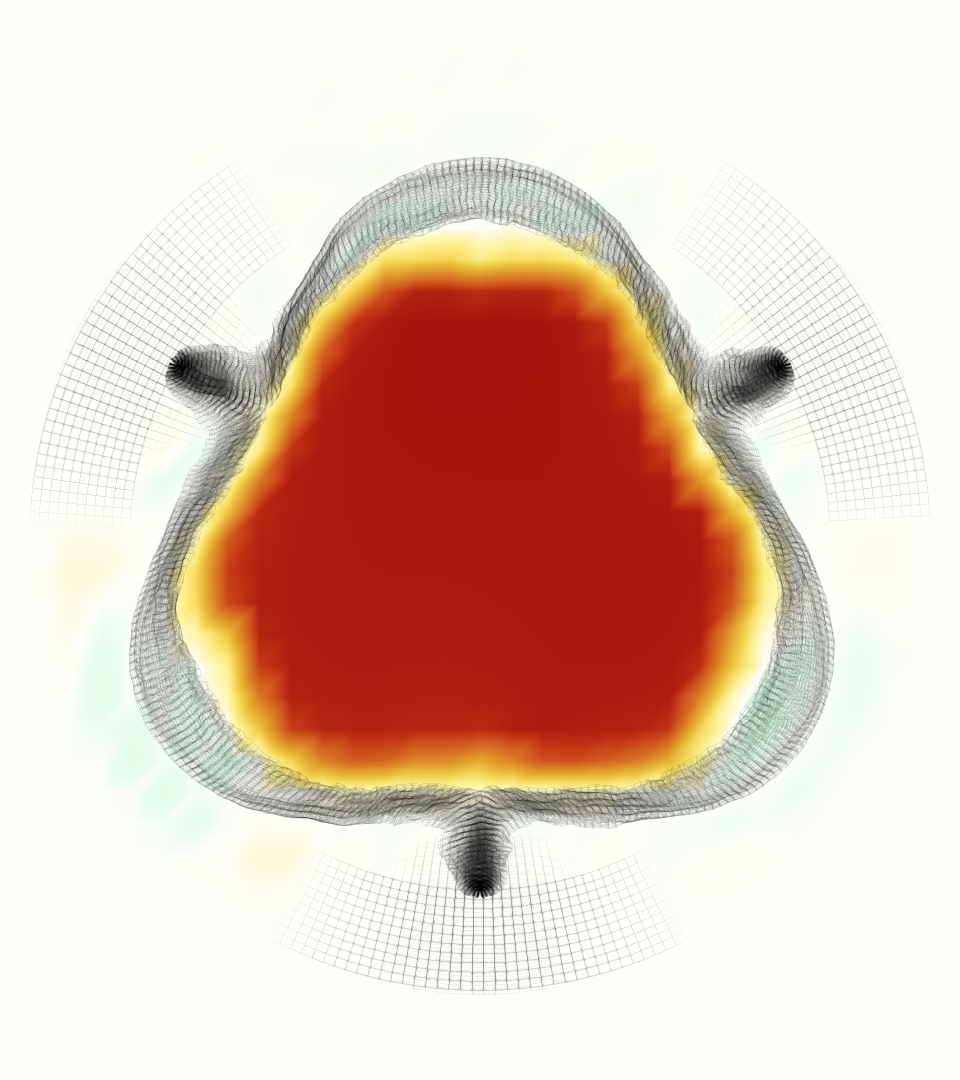

The gross morphology of the model valve that emerged from this process is shown in Figure 4. The free edge was 2.87 cm, corresponding to 3.3 cm in the predicted loaded configuration. After the pinching the leaflets together at the commissures, this left approximately 2.1 cm of free edge rest length per leaflet free to move independently of the other leaflets, within measurement error of ±0.1 cm from the free edge length of 2.2 cm measured on the prostheses. The leaflet rest height was 0.94 cm corresponding to a predicted loaded height of 1.44 cm. The measured leaflet height of 1.3 cm is nearly the predicted loaded height of 1.44 cm, which may be because the leaflets are so compliant in the radial direction, that pulling them flat to measure them achieved substantial stretches. The fiber orientation of the model runs from commissure to commissure and qualitatively matches experimental observations [38], though direct quantitative comparison is beyond the scope of this work. One minor limitation is that we do not add bending rigidity to the leaflets, beyond what emerges from the thickening process described above, and thus may not accurately capture leaflet flutter or other similar behaviors. Based on the thickness of mm, we estimated the mean tangent modulus at the predicted loaded stretches as dynes/cm2 circumferentially and dynes/cm2 radially. The prosthetic valve tissue is fixed in glutaraldehyde, and literature values for the fully-recruited circumferential tangent modulus of fixed porcine aortic valve tissue vary widely. Based on the experimental measurements of Billiar and Sacks and their constitutive law for valves fixed under 4 mmHg of pressure, we evaluated their constitutive law at the relevant stretches and and estimated the circumferential tangent modulus to be dynes/cm2 [6]. Rousseau et al. reported moduli ranging from to dynes/cm2, depending on the applied preload during fixation [36]. Sung et al. reported moduli ranging from to dynes/cm2, depending on fixation pressure [43]. Thus our estimated tangent modulus falls within the range of existing studies, so we considered our resultant modulus in good agreement given the complexity of the steps involved, phenomenological nature of the constitutive law and uncertainties in experiments. We do not have access to the precise material properties of the prosthetic valve, and further, the only literature we could find on the material properties of a similar prostheses reported the tangent modulus at one particular loading, which did not appear to be at a relevant stretch for comparisons with our model [19]. Thus, our model has material properties in a reasonable range for a fixed aortic valve prostheses (placed in the pulmonary position in our simulations), but it does not directly model the material properties of the prostheses.

We constructed the model vessel for FSI simulations from data from the MRI scans (Figure 4). The signal magnitude of 3D printed model material is distinct from the signal of the fluid in the scans, and we applied a thresholding operation to generate a three-dimensional model of the printed vessel surface. Using the MRI data ensured that the MRI and simulation coordinates were consistent in space and there were no alignment or registration errors. While using the files that generated the 3D printed model would have offered more spatial fidelity, the potential error in flow fields due to any mis-registration would have likely been much more substantial. Using Meshmixer (San Rafael, CA), we smoothed the mesh to remove stair-step effects and removed artifacts from the valve scaffold. We then remeshed to the desired edge length of 0.25 mm and extruded the model 0.25 mm and 0.5 mm to create a three-layer structure. As in the valve, this serves to eliminate the “grid aligned artifact” that can occur with pressure differences across thin membranes in the IB method [16]. Flow extenders of length 1 cm were added to the vessel at the inlet and both outlets to ensure that the normal to the vessel was aligned with the normal of the fluid box at the inlets and outlets. In FSI simulations, the vessel was held in place using target points, stiff springs of zero rest length that connect the current position of each model node to its desired position (Section 3.3). Additional linear springs are placed on each edge in the triangulated model. These springs are not meant to model a particular material and only serve to keep the vessel rigid and stationary throughout the simulation.

At = 0, the axial slice directly at the valve annulus shown in columns 1 and 2 in Figure 6, there was excellent agreement between the simulation and experiment over the cardiac cycle in the speed and shape of the jet through the valve. In both cases, the axial velocity increased as the flow accelerated during systole and the valve leaflets opened, then decreased during diastole with slight negative velocity before the valve leaflets were fully closed. The forward flow through the valve annulus did not form a full circle, but rather developed a triangular shape with a point of the triangle forming along the interior curve of the vessel, at the bottom of the axial slices. At = 0, the points of this triangular jet shape aligned with the commissures of the valve. This shape persisted during peak systole and was well-matched by the simulation.

The axial slice = 0.625 cm, shown in columns 3 and 4 in Figure 6, cut through the support scaffolding of the valve and the leaflets when they are open. In the experimental data, the shape of the jet changed as it moved downstream. A triangular shape occurred, but the points were then aligned with the middle of each open leaflet as opposed to the commissures. Those points were also more rounded than they were at = 0. The peak velocity of the jet was faster at = 0.625 cm than at = 0, as the flow accelerated through the open valve leaflets. The simulation produced these features at = 0.625 cm. The triangular shape of the jet shifted similarly, and its speed increased compared to the upstream slice. As the flow decelerated into diastole, the jet shape remained roughly triangular but diminished in intensity before disappearing after valve closure.

The jet continued to develop at = 1.25 cm, an axial slice immediately downstream of the valve scaffolding and open leaflets, shown in columns 5 and 6 in Figure 6. In the experimental data, the points of the triangular jet shape extended further towards the vessel wall. In addition, regions of reversed flow developed in the locations downstream of the commissures, resulting in curved sides to the shape of the jet. Each tip of the jet was unique, due to variations in the individual leaflets in the physical bioprosthetic valve. These variations are apparent in the velocity fields, possibly because the jet edges are similar enough cycle to cycle that irregularities are still being captured even with phase averaging. Further discussion of these features can be found in Schiavone et al. [39], which showed that the jet tip shapes occurred in different pulmonary anatomies, demonstrating that they were likely due to inherent properties of each leaflet. The leaflets in the mathematical model of the valve are identical, so these nuances in leaflet variation could not be replicated. The simulation did capture some of the extension of the tips of the jet, as they were closer to vessel wall at slice = 1.25 cm than = 0.625 cm. The curves in the triangular sides of the jet were also present in the simulation, though they were less pronounced than the experimental data. At both = 0.625 cm and = 1.25 cm, the jet shape in the simulation was smoother than the jet in experiment. It is possible that the free edges of the leaflets in the mathematical model are not fully replicating the behavior of the physical leaflets of the bioprosthetic valve, in particular the amplitude or frequency of leaflet flutter, leading to the variations seen in the jet shape at = 1.25 cm downstream of the leaflet edges. The simulation, however, does capture the key features of the triangular shape and speed of the jet. Overall, qualitative comparisons demonstrated that the simulation reproduced key features of the flow during systole and diastole.